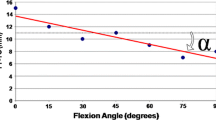

To answer the second research question, the analyses by Nägerl et al. [11] and Pinskerova et al. [14] were taken into account. These studies showed that the contact areas of the femoral condyles on the tibial plateau move backwards during knee flexion. Under weight-bearing conditions, the contact point between the medial femoral condyle and the tibial plateau averaged a distance of 29 and 22 mm measured from the ipsilateral posterior tibial cortex in 20° and 90° of knee flexion, respectively. This means that a difference of the medial and lateral tibial plateau inclination would influence femoral rotation by means of a different height between the posteromedial and posterolateral femorotibial contact points as illustrated in Fig. 4a and b. Thus, the medial-to-lateral tibial slope asymmetry was assessed as the intra-individual difference between the medial and lateral tibial plateau inclination. This means that the tibial slope asymmetry had a positive sign in cases where the medial slope was steeper than the lateral slope, and had a negative sign in cases where the medial slope was flatter than the lateral slope.

Illustrated is the effect of tibial slope asymmetry on femoral rotation by means of a difference in height between the medial and lateral tibial plateau in 20° and 90° of knee flexion. In the frontal view, the maximal observed effect on internal and on external femoral rotation is shown in comparison with the neutral position of the femoral condyles in both knee flexion angles

The effect of tibial slope asymmetry on femoral rotation was calculated mathematically by means of radian measure with the knee positioned in 20° and 90° of knee flexion. First, the value of tibial slope asymmetry (in degrees) was converted into radian according to the formula rad = deg π/180. This value was then multiplied either by 23 mm or by 30 mm, representing the difference in height (in mm) between the posteromedial and posterolateral contact points in 20° or 90° knee flexion. The value of 23 and 30 mm resulted from the length of the tibial head in the sagittal plane (Ø 52 mm; n = 35) minus the distance from the posterior tibial cortex to the medial femorotibial contact point (29 mm for 20° of knee flexion; 22 mm for 90° of knee flexion), according to Pinskerova et al. [14]. Subsequently, the differences in height were divided by the distance between the centre of the medial and lateral femoral condyle in the frontal plane (Intercondylar distance: Ø 44 mm; n = 35) representing the value of femoral rotation in radian. Values of radian measures were then converted into degrees (deg = rad 180/π) representing internal femoral rotation in cases of positive values and external femoral rotation in cases of negative values.

Severity of trochlear dysplasia was significantly associated with an asymmetric inclination of the tibial plateau (Table 1). Whereas the medial tibial slope showed identical values between controls and study patients (n.s.), lateral tibial plateau inclination becomes flatter with increasing severity of trochlear dysplasia (p < 0.01) (Table 1; Fig. 5). Consequently, the intra-individual slope asymmetry increased steadily towards positive values (p < 0.01) and therefore increased internal femoral rotation in 20° and in 90° of knee flexion in patients with severe trochlear dysplasia (p < 0.01) (Table 1; Fig. 6). Though tibial slope asymmetry showed a relatively wide range in both study and control patients, study patients were more frequently found than controls among the 20 largest positive values of tibial slope asymmetry (6°–10°). On the other hand, among the 20 largest negative values of tibial slope asymmetry (−4° to −8°), control patients were more often found than study patients (p = 0.024). Concomitantly, this means that the extreme values of internal femoral rotation were more pronounced in patients with LPD, whereas the extreme values of external femoral rotation were more pronounced in control subjects. The study group also showed a slightly increased valgus deformity expressed by a smaller aDLFA (p < 0.01), whereas the mPMTA did not differ between study and control subjects (n.s.). Interrater and intrarater reliability was near-perfect for the investigated parameters with a clearly positively significant correlation between the two measurement series (Table 2a, b).

To the best of our knowledge, this is the first study that investigated the association between LPD and tibial plateau geometry. In addition, this study aims to provide an initial understanding of medial-to-lateral tibial slope asymmetry and the resultant biomechanical characteristics of the tibiofemoral joint with its relevant contributions to lateral patellar instability. If one considers the mean values of tibial slope asymmetry and femoral rotation, it could be argued that they may not have a dramatic effect on the biomechanics of the knee joint. However, the important point to consider is the differences between the extreme values of internal femoral rotation (5.5° in 20° knee flexion; 7.2° in 90° knee flexion) in patients with patellar instability and that of external femoral rotation (−4.2° in 20° knee flexion; −5.5° in 90° knee flexion) in control subjects. In addition, further limitations were noticed and deserve mention. First, as already stated by Hashemi et al. [5], it is important to note that the access to a sufficient length of the femur and tibia in the magnetic resonance image and the ability to identify landmarks, precisely all, could have an impact on the slope measurements. Second, slope measurements were referenced on the bony landmarks in the centre of the medial and lateral tibial plateau, but knee joint morphology is further characterized by the cartilage surface that is concave medially and convex laterally. This means that the articular surface is higher on the lateral side and lower on the medial side when compared to the bony landmarks used in this study. This in turn, however, would enhance the observed effect on internal femoral rotation during knee flexion rather than diminish it. Finally, our analyses were based on an idealized mathematical model with the knee positioned in 20° and 90° of knee flexion. It was not able to evaluate the effect of tibial slope asymmetry on tibiofemoral biomechanics during varying degrees of knee flexion. If one considers that the patella becomes least stable between 0° to 30° of knee flexion [16], it could be argued that an increase in internal femoral rotation may not have a dramatic effect on patellar instability in higher degrees of knee flexion. However, though most patellae dislocate from a nearly straight start followed by a movement to flexion, there is a certain amount of patients dislocating their patellae from a well-bent start followed by either knee extension or flexion [12]. Thus, it seems likely that an increase in internal femoral rotation contributes relevantly to patellar instability even in higher degrees of knee flexion.